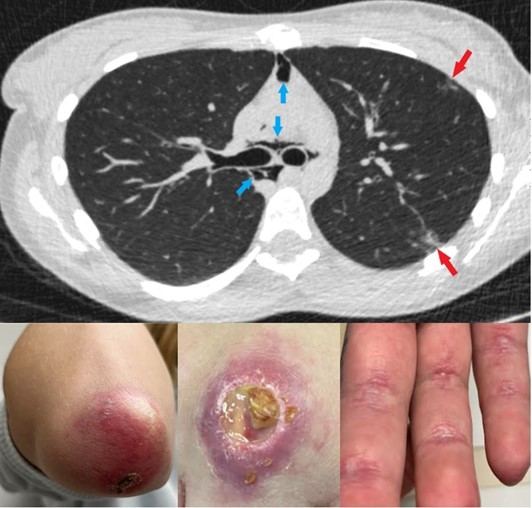

Pneumomediastinum & Ulcerative Cutaneous Dermatomyositis

These images depict a 22-year-old woman with a recent diagnosis of anti-melanoma differentiation-associated gene 5 (MDA-5) antibody dermatomyositis who sought evaluation of worsening skin rashes and pleuritic chest pain. On examination, the patient was found to have heliotrope rash of the eyelids, digital pulp, third metacarpophalangeal joint ulcerations and Gottron’s sign of the elbows. A computed tomography (CT) chest scan showed moderately sized pneumomediastinum (blue arrows) dissecting into deep neck spaces and multifocal peripheral reticular opacities (red arrows) consistent with early interstitial lung disease (ILD).

These images depict a 22-year-old woman with a recent diagnosis of anti-melanoma differentiation-associated gene 5 (MDA-5) antibody dermatomyositis who sought evaluation of worsening skin rashes and pleuritic chest pain. On examination, the patient was found to have heliotrope rash of the eyelids, digital pulp, third metacarpophalangeal joint ulcerations and Gottron’s sign of the elbows. A computed tomography (CT) chest scan showed moderately sized pneumomediastinum (blue arrows) dissecting into deep neck spaces and multifocal peripheral reticular opacities (red arrows) consistent with early interstitial lung disease (ILD).

Anti-MDA-5 antibody dermatomyositis represents an aggressive subset of myositis that can involve ulcerative cutaneous disease, rapidly progressive ILD, and rarely, spontaneous pneumomediastinum.

Because anti-MDA-5 antibody dermatomyositis is a heterogeneous disease with many possible manifestations, it is important to evaluate specific lab parameters, such as white blood cell count, lymphocyte count, C-reactive protein and ferritin, to fully assess the patient and help identify disease subtypes. For more information, visit https://tinyurl.com/2wzwb4wn and review the section on IIMs.